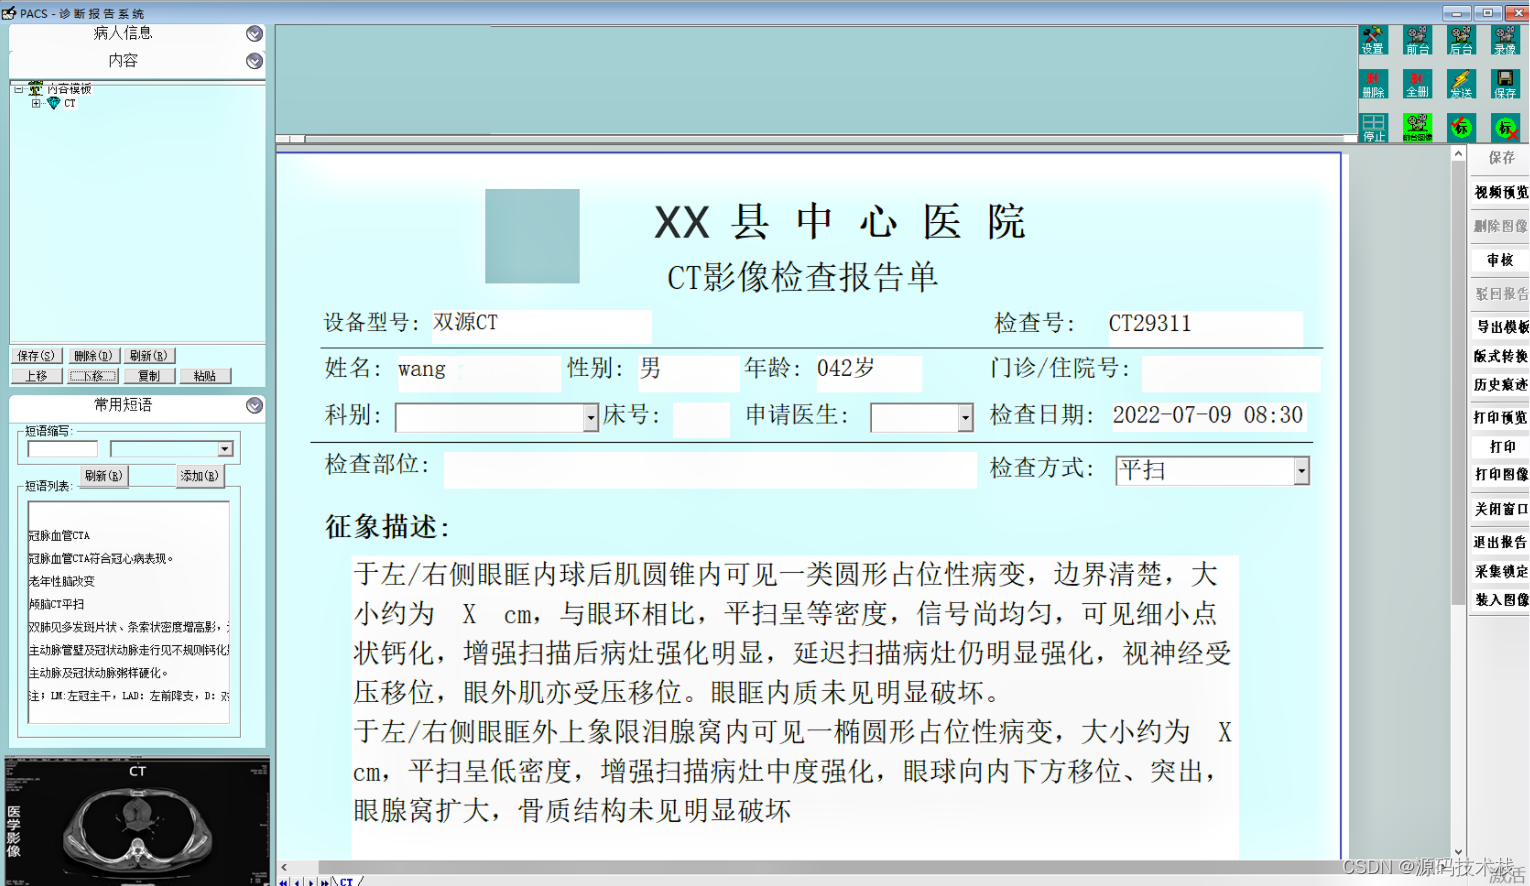

影像报告:PACS可以生成影像报告,将医生的诊断结果和建议以文字形式记录下来,并与相应的影像数据关联起来。这样可以方便医生之间的交流和患者的随访。

功能包括:预约分诊、排队叫号、放射/医技科室信息管理系统、影像处理、医技报告书写、WEB图像浏览(院内)、影像报告发放/共享。